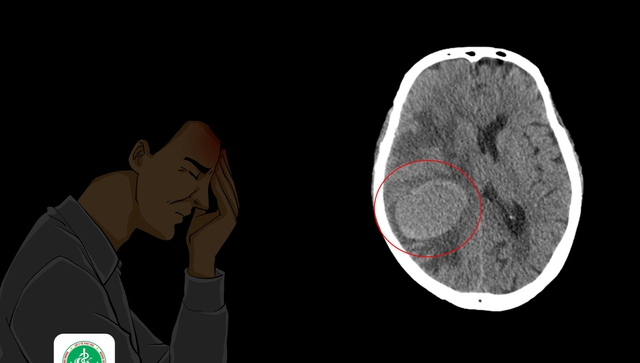

Vừa qua, các bác sĩ ở Trung tâm Y tế huyện Cẩm Khê, Phú Thọ cho biết đã tiếp nhận và điều trị cho nam bệnh nhân (75 tuổi, ở Phú Thọ) u não thứ phát, nguyên nhân sâu xa xuất phát từ ung thư phổi giai đoạn cuối.

Theo lời bệnh nhân, ngoại trừ triệu chứng yếu nửa người trái, mọi thứ đối với bệnh nhân đều rất bình thường. Tuy nhiên, qua thăm khám, các bác sĩ nghi ngờ bệnh nhân bị đột quỵ não nên đã chỉ định chụp cắt lớp vi tính sọ não.

Kết quả chụp cho biết: Nhu mô não vùng thái dương phải có khối tăng tỉ trọng kích thước 45x55 mm, bờ ranh giới rõ, khối gây đè ép não thất bên bên phải và đè đẩy đường giữa lệch qua trái.

Quá bất ngờ trước kết quả chụp, gia đình xin không thực hiện thêm các thăm dò khác, lập tức xin chuyển đến Bệnh viện K. Tại đây, các bác sĩ kết luận khối u não chỉ là thứ phát, nguyên nhân sâu xa xuất phát từ ung thư phổi giai đoạn cuối.